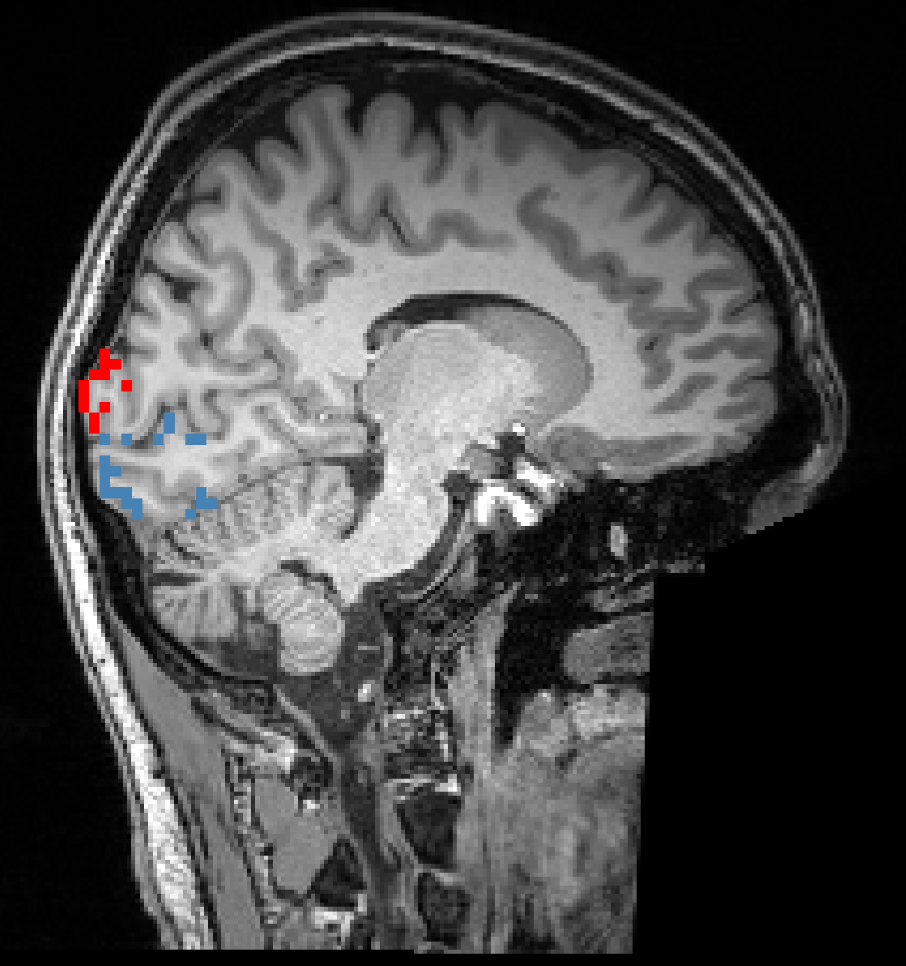

Subcortical ROIs

This is the state-of-the-art for anatomically-based ROI definition based on deep learning